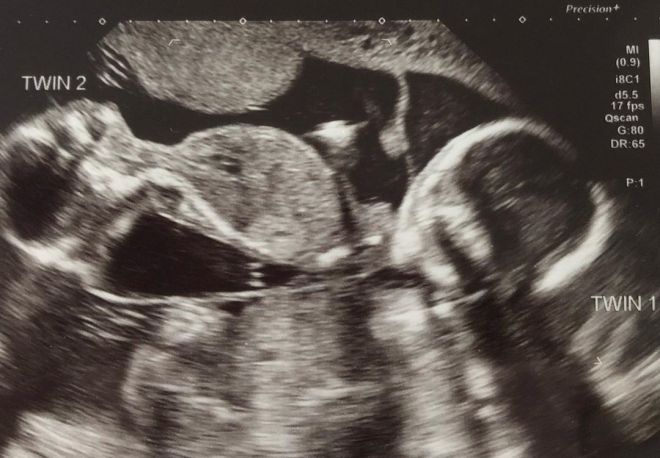

Ребекка Робертс и ее супруг Рис Уивер стали родителями близнецов. Их история поразила Сеть. Многие пользователи отметили, что она достойна стать основой мелодрамы. Дело в том, что пара несколько лет лечилась от бесплодия. Затем наступила долгожданная беременность. Сюрприз ожидал во время УЗИ, когда Ребекка Робертс была на 12-й неделе беременности.

Это было шоком, когда мне сказали, что развиваются два ребенка вместо одного, — вспоминает британка. — Затем они сказали мне, что между двумя младенцами разница в 3 недели, которую врачи не могут понять.